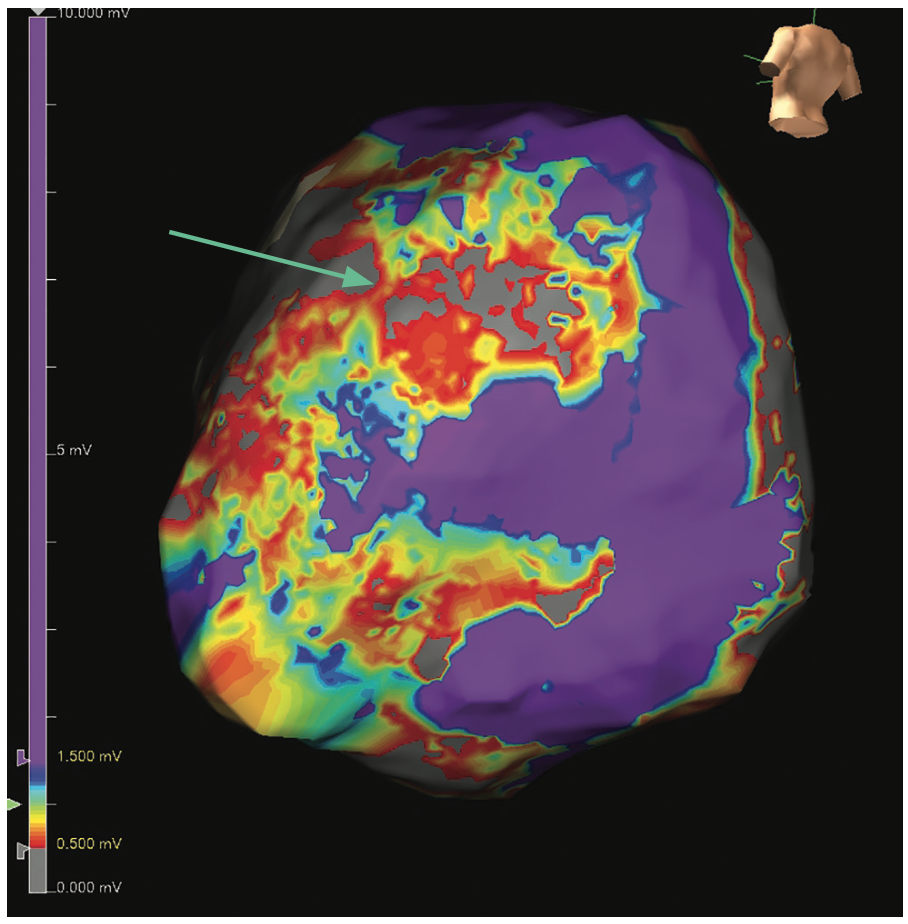

Epicardial access was obtained with a 12 cm micropuncture needle (Cook Medical). An 8 French Pinnacle sheath (Terumo) was placed into the pericardial space. A baseline epicardial voltage map was created using an Advisor HD Grid Mapping Catheter, Sensor Enabled (Abbott) and EnSite X EP System (Abbott) (Figure 1). The map showed an epicardial voltage bridge (green arrow) in the middle of 2 regions of more dense scar.